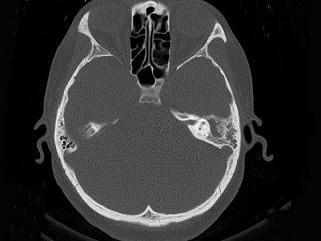

女,34岁,左耳鸣,听力下降两个月,PE:左外耳道有脓性分泌物,鼓膜充血水肿,左中耳腔内软组织影,CT检查如图,最可能诊断为 ( )